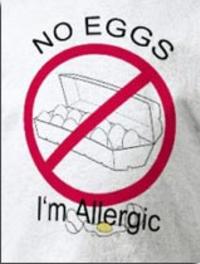

L’éviction est la seule mesure actuellement recommandée en cas d’allergie à l’œuf. Celle-ci étant particulièrement difficile, la recherche [...]